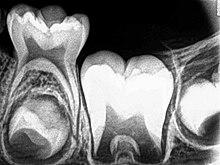

Dentin

Dentin formation, known as dentinogenesis, is the first identifiable feature in the crown stage of tooth development. The formation of dentin must always occur before the formation of enamel. The different stages of dentin formation result in different types of dentin: mantle dentin, primary dentin, secondary dentin, and tertiary dentin.[31]

Odontoblasts, the dentin-forming cells, differentiate from cells of the dental papilla. They begin secreting an organic matrix around the area directly adjacent to the inner enamel epithelium, closest to the area of the future cusp of a tooth. The organic matrix contains collagen fibers with large diameters (0.1–0.2 μm in diameter).[32] The odontoblasts begin to move toward the center of the tooth, forming an extension called the odontoblast process.[1] Thus, dentin formation proceeds toward the inside of the tooth. The odontoblast process causes the secretion of hydroxyapatite crystals and mineralization of the matrix. This area of mineralization is known as mantle dentin and is a layer usually about 150 μm thick.[32]

Whereas mantle dentin forms from the preexisting ground substance of the dental papilla, primary dentin forms through a different process. Odontoblasts increase in size, eliminating the availability of any extracellular resources to contribute to an organic matrix for mineralization. Additionally, the larger odontoblasts cause collagen to be secreted in smaller amounts, which results in more tightly arranged, heterogeneous nucleation that is used for mineralization. Other materials (such as lipids, phosphoproteins, and phospholipids) are also secreted.[32]